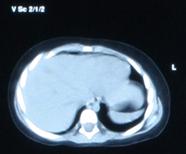

Fig. nr. 268. Formatiune anecogena abdominala fetala independenta de rinichi, la 28 sapt,ulterior in crestere la copilul de 3 ani

Fig. nr. 269. La peste 3 ani de la diagnosticul intrauterin, formatiunea tumorala abdominala ajunge la dimensiunea de 12 cm diametru si cu o structura inomogena cu mici hiperecogenitati sugestive ptr un teratom

Fig. nr. 270. Formatiunea tumorala explorata echo in figura anteorioara, acum la computer tomografie, in raport cu ficatul. Intraoperator s-a gasit un teratom retroperitoneal.